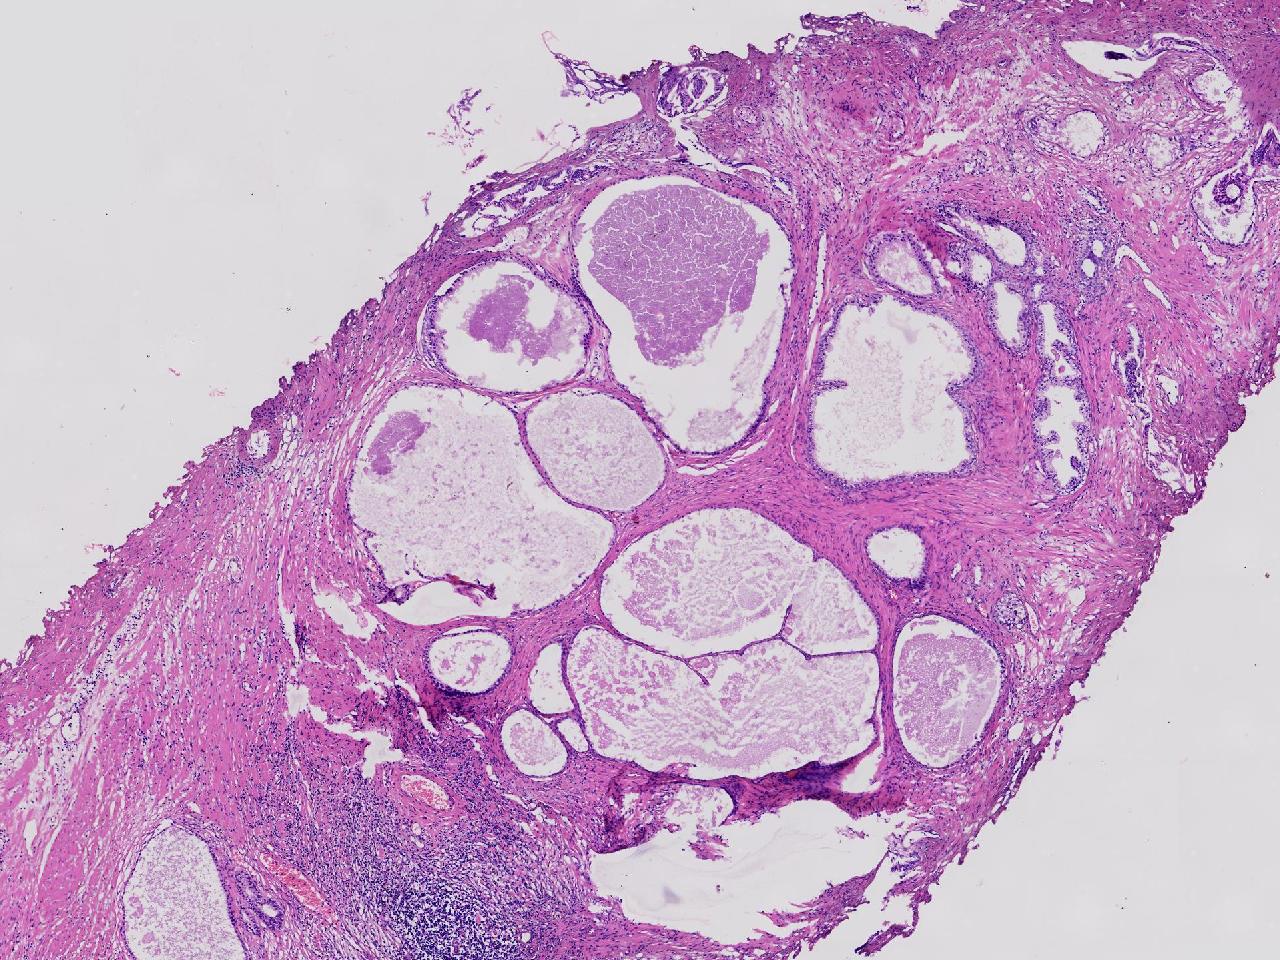

良性前列腺增生吧?

性别

男

年龄

65岁

临床诊断

前列腺电切组织

一般病史

进行性排尿困难半年余。

标本名称

前列腺

大体所见

灰粉色条索状软组织多块,4X3X3厘米。

图1

、良性前列腺增生

BPH.